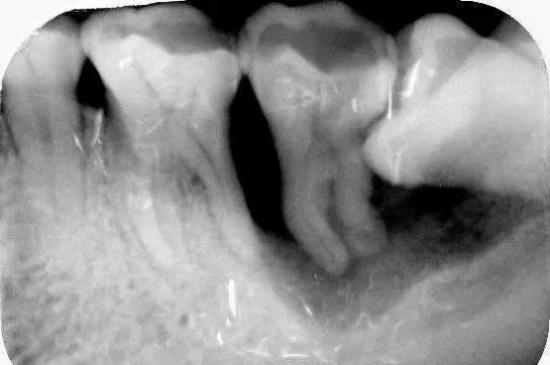

2.龋齿:阻生的智齿与第二磨牙之间容易积存食物残渣,而且不易清洁,很容易形成智齿和第二磨牙的龋齿而发生疼痛。

5.邻牙及支持组织的吸收:当阻生的智齿萌出过程中受阻于第二磨牙时,会引发第二磨牙牙根逐渐吸收,严重者可使下颌第二磨牙远中牙根完全吸收,致第二磨牙松动、疼痛。阻生智齿与第二磨牙间常食物嵌塞发生慢性牙周炎,也会造成牙槽骨的炎症性吸收,使第二磨牙反复肿痛。